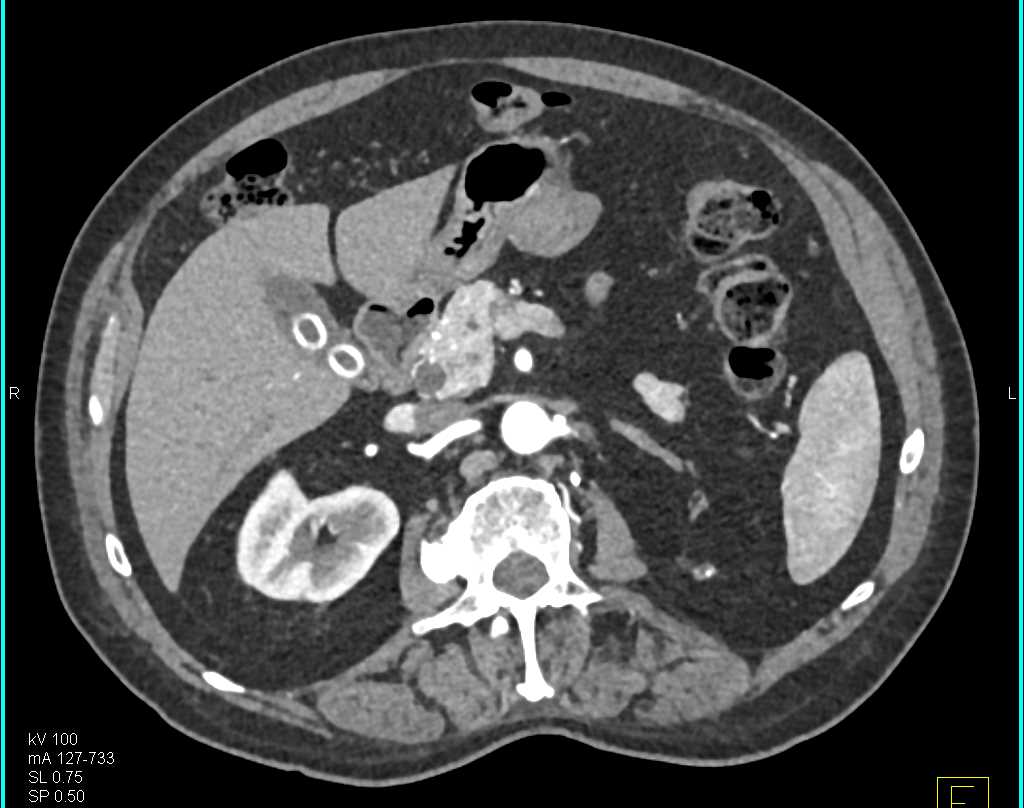

Gastric Duplication Cyst